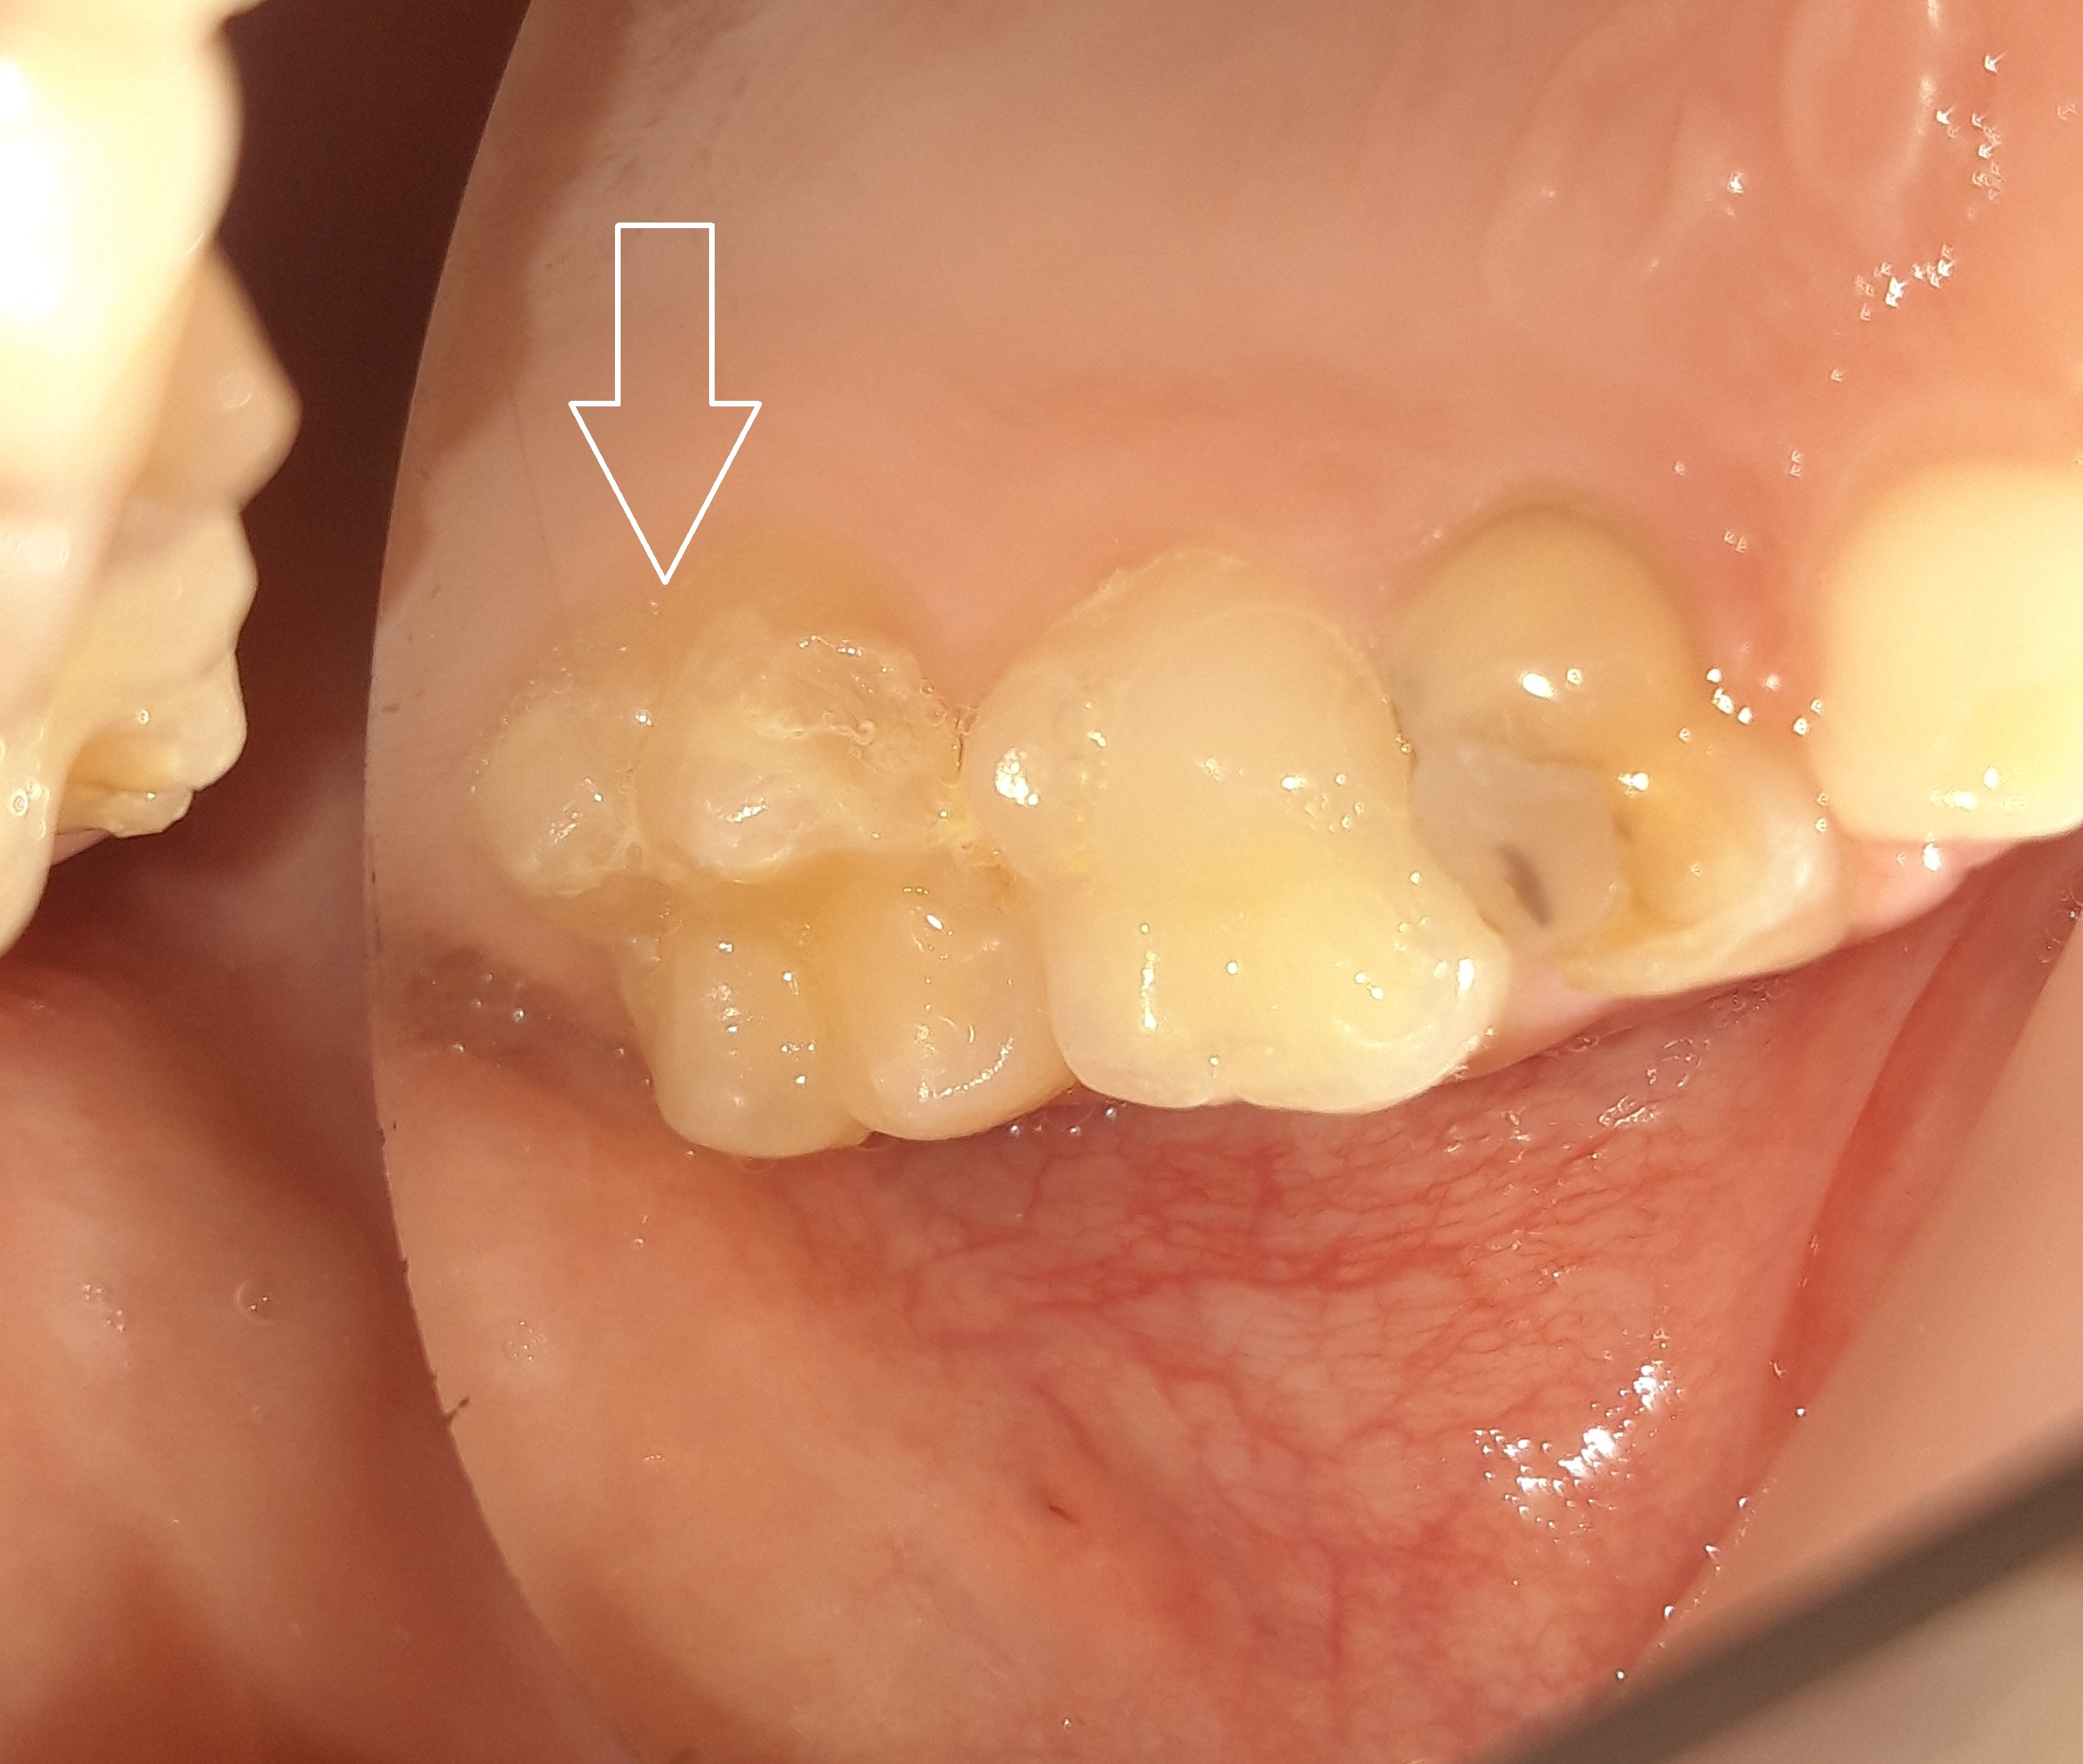

Περιστατικά – Sealant / προληπτική κάλυψη οπών και σχισμών

Στο συγκεκριμένο ασθενή πραγματοποιήθηκε ταυτόχρονα αφαίρεση της επιφανειακής αρχόμενης τερηδόνας και προληπτική κάλυψη οπών και σχισμών (sealant) στη μασητική επιφάνεια του άνω αριστερού πρώτου γομφίου.